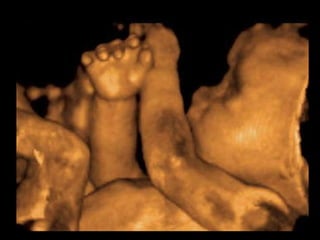

Este documento describe brevemente la historia de la radiografía y los rayos X, y explica que existen diferentes tipos de radiografías y aplicaciones en odontología, incluyendo radiografías intraorales y extraorales. También proporciona ejemplos de actividades para identificar estructuras que aparecen en radiografías dentales de acuerdo a su radioopacidad.